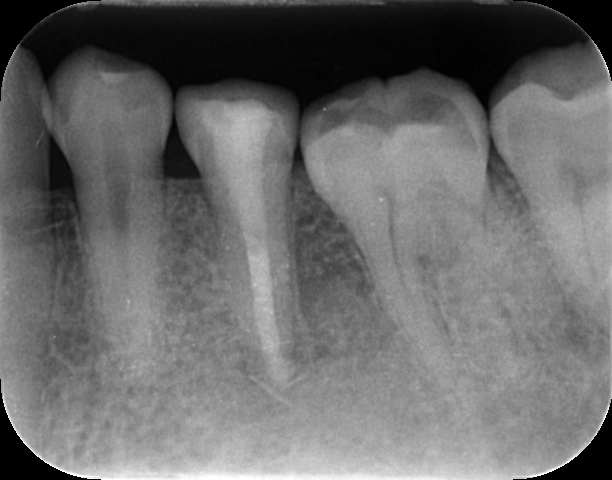

根管治療を終えて3ヶ月経過を観察したところ、10mmあったポケットは消失し、正常値に改善。レントゲン上の影も劇的に回復しました。

現在はセラミッククラウンを装着し、術後1年半が経過しましたが、痛みや違和感もなく、ご自身の歯でしっかりと噛めています。正確な診断さえあれば、救える歯がある。私たちはそう信じて日々の診療にあたっています。